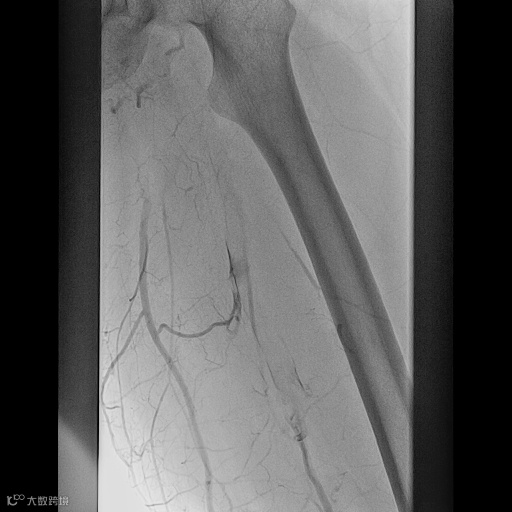

由沈阳市第一人民医院介入科陈建军主任团队运用中天天航™Pro血栓抽吸导管治疗一例急性左下肢深静脉血栓形成且伴有右下肢血流淤滞病变,成功清除血栓并快速恢复肢体灌注,欢迎大家阅读、分享、交流!

手术过程